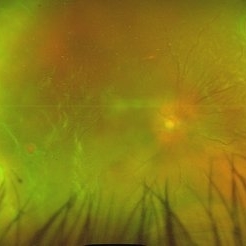

Occlusive Vasculitis Occlusive VasculitisJan 28 2023 by Anjana Mirajkar, MS Ophthalmology Widefield color image of RE of a 40 year old female a case of occlusive retinal vasculitis. Photographer: Dr. Anjana Mirajkar -Retina Foundation, Ahmedabad Condition/keywords: occlusive retinal vasculitis